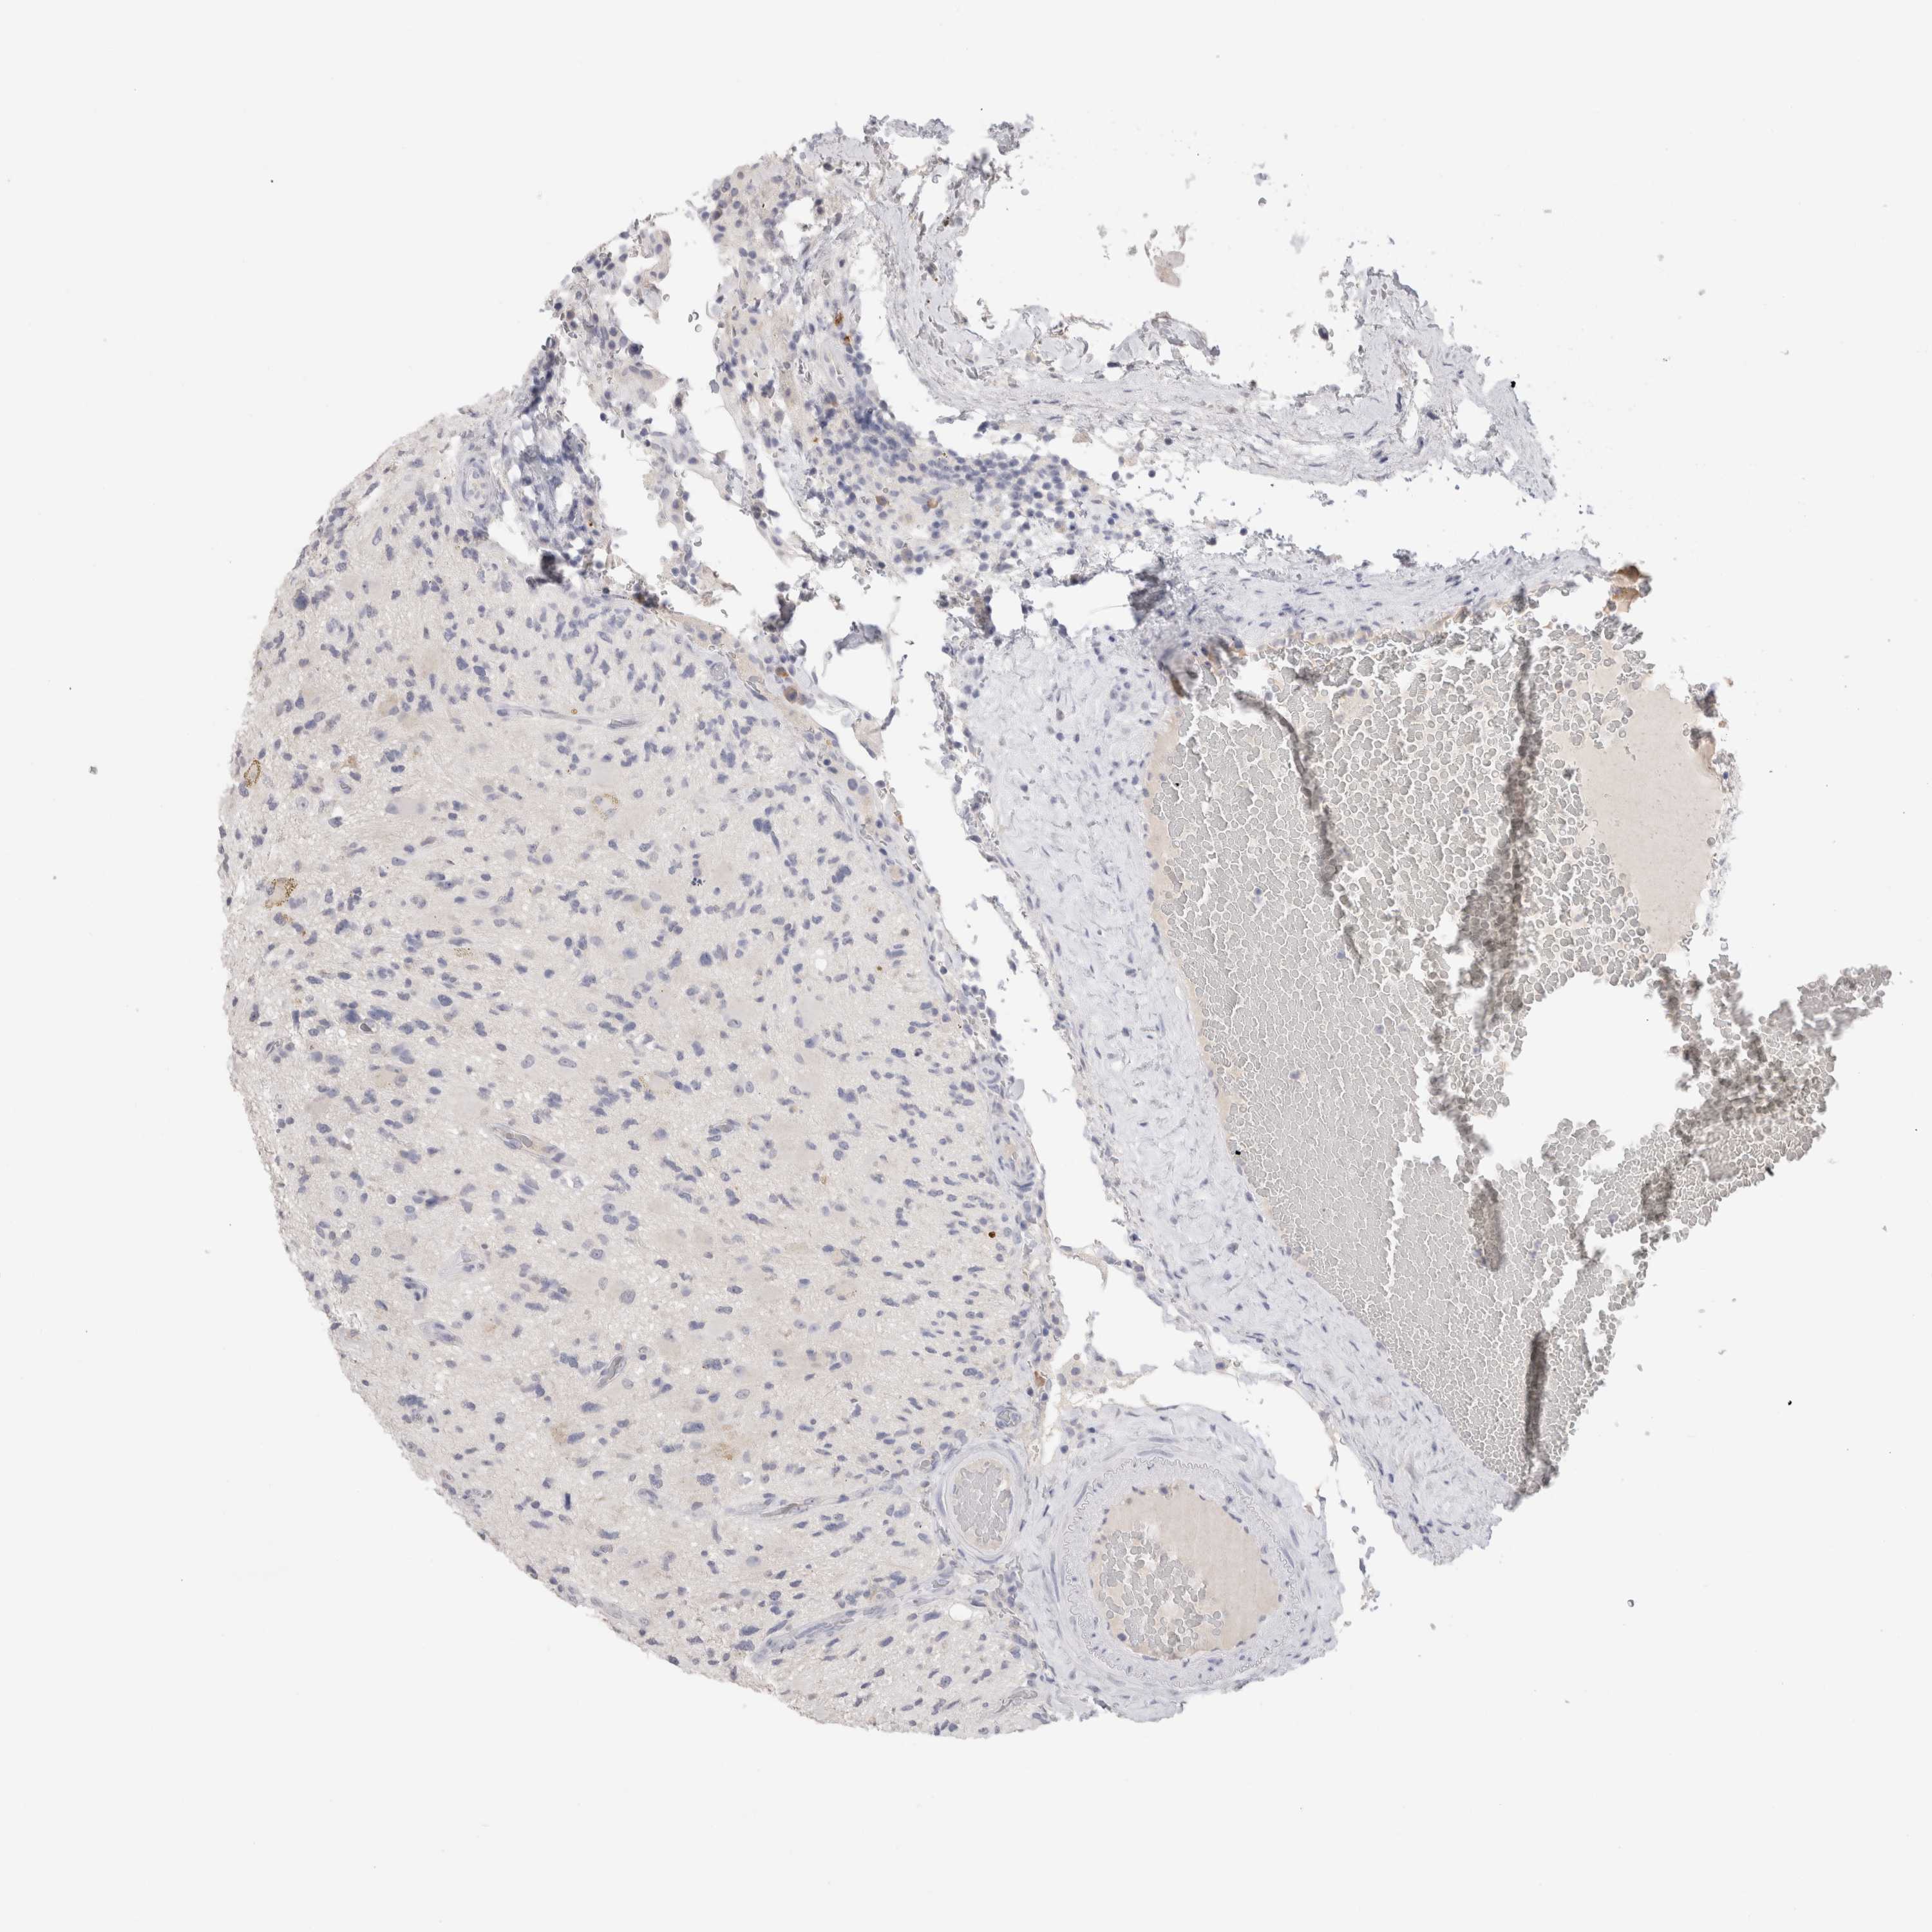

GLIOMA - Protein expressioni

A mouse-over function shows sample information and annotation data. Click on an image to view it in a full screen mode. Samples can be filtered based on level of antibody staining by selecting one or several of the following categories: high, medium, low and not detected. The assay and annotation is described here.

Note that samples used for immunohistochemistry by the Human Protein Atlas do not correspond to samples in the TCGA dataset.

Antibody stainingi

Antibody staining in the annotated cell types in the current human tissue is reported as not detected, low, medium, or high, based on conventional immunohistochemistry profiling in selected tissues. This score is based on the combination of the staining intensity and fraction of stained cells.

Each image is clickable and will lead to virtual microscopy that enables deeper exploration of all samples and also displays staining intensity scores, fraction scores and subcellular localization as well as patient and tissue information for each sample.

Antibody HPA051467

Antibody CAB025133

Staining

High

Medium

Low

Not detected

Intensity

Strong

Moderate

Weak

Negative

Quantity

>75%

75%-25%

<25%

None

Location

Nuclear

Cytoplasmic/membranous

Cytoplasmic/membranous,nuclear

Glioma, malignant, High grade

Glioma, malignant, Low grade